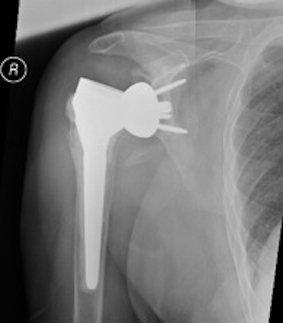

Loosening

Failed Glenoid Reverse TSRReverse TSR Loose Metaglene

Loose metaglene

hum shafthum shaft

Lysis around humeral and glenoid component

Reverse TSR Loose Glenosphere from Metaglene

Glenosphere loosening from metaglene